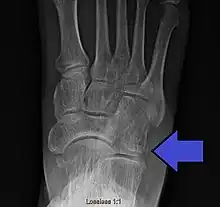

| Avulsion fracture of the right cuboid bone of the foot | |

A cuboid fracture is a fracture of the cuboid bone of the foot. Diagnosis is by X-ray imaging, magnetic resonance imaging, or bone scan.[1] Treatment may be conservative or involve surgery, depending on the type of fracture.[1] They are rare.[1]